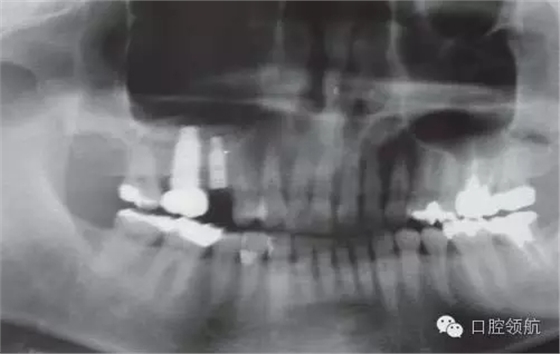

患者10年前,在外院于( 左上第六顆牙)區(qū)行上頜竇底提升術(shù)同期植入種植體,經(jīng)過10年上頜竇內(nèi)生成骨完全吸收消失了(圖1)?;颊叽舜蝸碓菏且驗猷徰? 左上第五顆牙) 不能保存,希望行種植修復(fù)治療。

圖1 術(shù)前牙片。由于上頜竇底黏膜提升植骨術(shù)而在上頜竇內(nèi)生成的骨已完全消失。